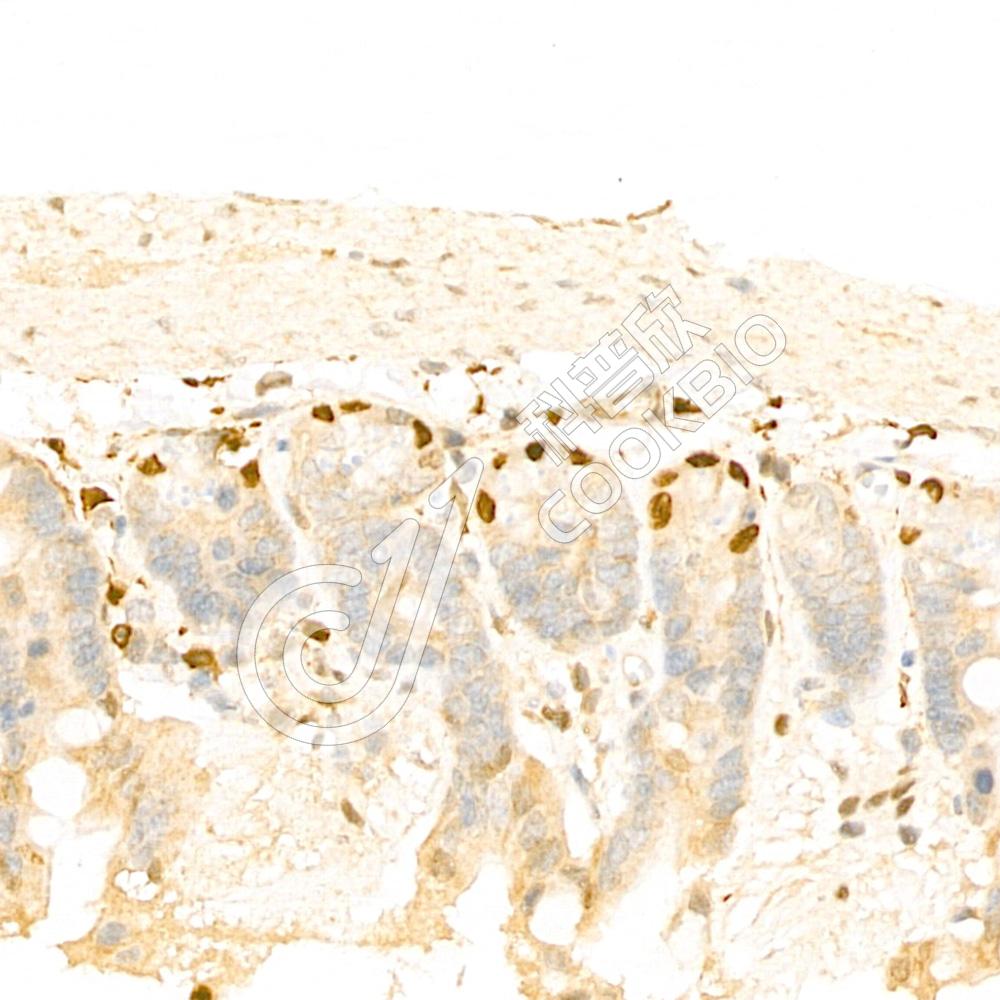

IHC检测GSK3 beta蛋白(货号 K133297).

样品: 大鼠睾丸, 4%多聚甲醛 (货号KSG1101) 固定12-24小时.

抗原修复: 柠檬酸抗原修复液(干粉, pH 6.0) (KSG1201), 98℃, 20分钟.

—抗: 1: 600稀释, 4℃ 孵育过夜.

二抗: S-vision免疫组化多聚二抗(山羊抗兔),即用型 (货号KB3906), 室温孵育20分钟.